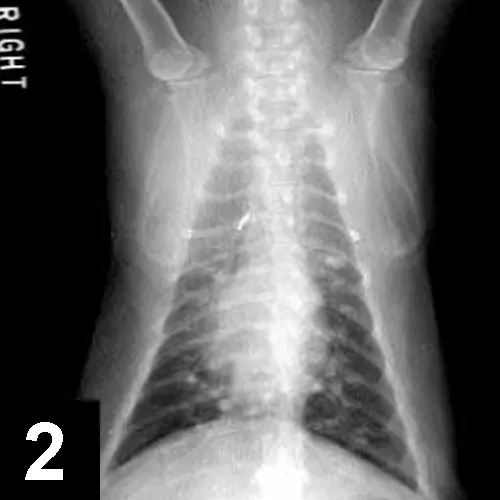

Diagnostics: CBC, chemistry panel, urinalysis, FeLV/FIV serologic testing, fecal analysis, and thoracic radiographs (Figures 1 and 2) were done initially (Table).

The cat is suspected of having underlying allergic airway disease, although this was not proven. Eosinophils were present in the nasal passages, airways, and blood and are commonly encountered in allergic disease. The mineralized pulmonary nodules seen on thoracic radiographs were thought to be due to dystrophic mineralization of chronically inflamed airways, although granulomas or metastatic disease could not be definitively ruled out.

Interpretation: Multifocal, mineralized, well-circumscribed nodules throughout the lung fields. A diffuse, moderate bronchointerstitial pattern is also present.